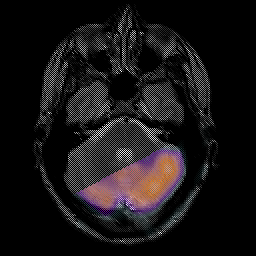

Glioma overlay -- Slice #7

[Home][Help][Clinical] Slice 7